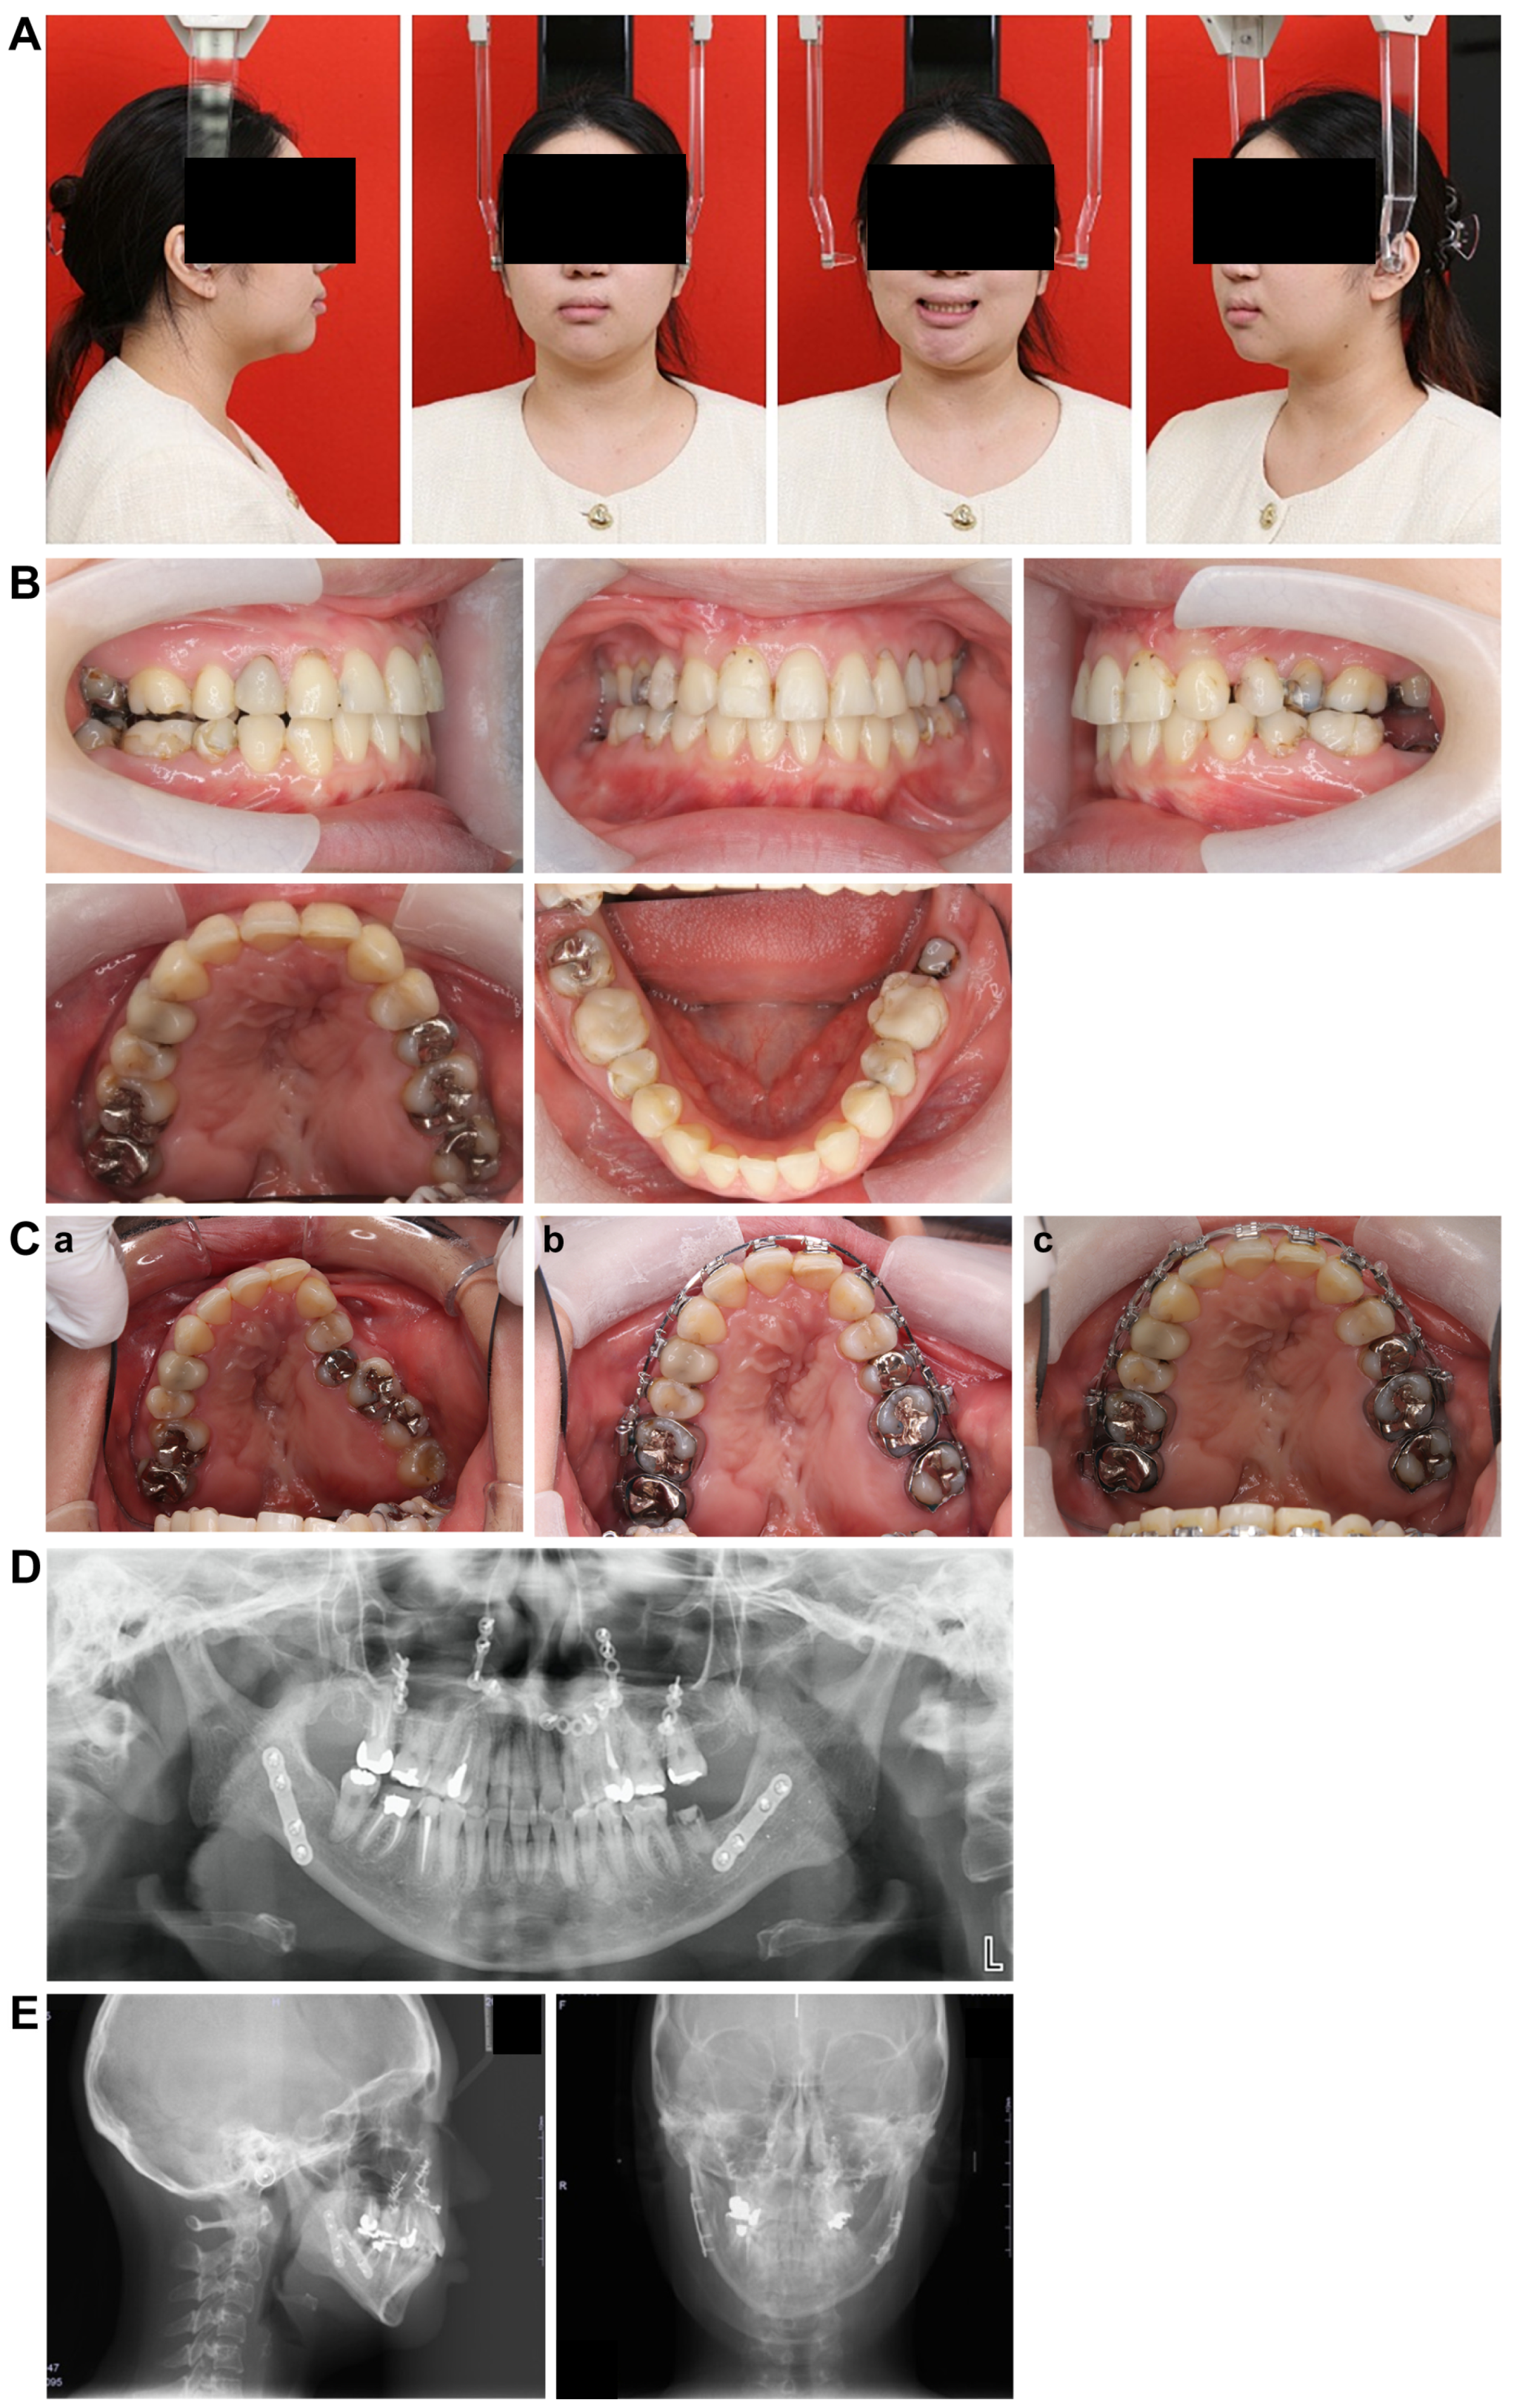

3.1. Initial Facial Findings (Figure 1A)

The frontal view showed facial asymmetry, with the left corner of the mouth elevated and a canted occlusal plane tilted upward on the left side when smiling. The lateral view revealed a concave profile with protrusions on the upper and lower lips. The esthetic line (E-line) measurements were −2.0 mm and +7.0 mm for the upper and lower lips, respectively, indicating a greater lower facial height relative to the upper facial height, suggesting an imbalance in vertical proportions.

3.2. Intraoral Photo at First Visit (Figure 1B)

The left maxillary dental arch was constricted and exhibited a crossbite. The anterior maxillary and posterior arch widths were 25.1 mm and 38.0 mm, respectively, with notable constriction in the anterior width. The molar relationship was classified as Angle Class III on the right side and Angle Class II on the left side. The overbite was +1.5 mm and the overjet was +2.0 mm. The arch length discrepancy was −3.0 mm and −3.9 mm in the maxilla and mandible, respectively, with mild crowding observed. The maxillary left lateral incisor was congenitally missing, and the mandibular right lateral incisor showed lingual displacement. Furthermore, oral hygiene was poor, with multiple prosthetic restorations in both the upper and lower jaws. In addition, the patient reported weak occlusal force on the left side and was unable to chew properly.

3.4. Lateral and Frontal Cephalometric Radiographs (Figure 2B)

The SNA angle (evaluation of the anteroposterior position of the maxillary alveolar base relative to the skull base) was 73.0°, and the SNB angle (evaluation of the anteroposterior position of the mandibular alveolar base relative to the skull base) was 72.0°. The ANB angle (evaluation of the anteroposterior positional relationship of the upper and lower alveolar bases) was +1.0°, the skeletal system was skeletal 1, and the plane angle of the lower edge of the mandible was 35.0°, indicating a high mandibular plane. The U1 to FH (maxillary central incisor axis angle) measured 104.0°, while the L1 to Mand.P (mandibular central incisor axis angle) was 86.5°, showing a lingual inclination of the maxillary central incisor axis.

A standard frontal head radiograph revealed a 2.0 mm deviation of the facial midline, mandibular deviation, a cant tilted upward to the left by 4.0°, facial asymmetry, and deformation of both the maxilla and mandible.